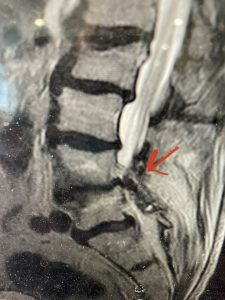

This 57 year-old male had a long history of low back pain and left lower extremity pain and numbness. The patient had failed conservative treatment of physical therapy and epidurals. MRI revealed tight left L2-3 and L3-4 lateral recess stenosis as well as significant right L4-5 facet arthropathy and right lateral recess stenosis as well as a grade 1 L4-5 spondylolisthesis

(Fig 2) Sagittal T2-weighted lumbar MRI demonstrating (arrow) tight lateral recess stenosis

It was felt that the patient should undergo surgical decompression and fusion at L4-5 given his spondylolisthesis. Post operatively he had an uneventful course and he had relief of his leg pain.